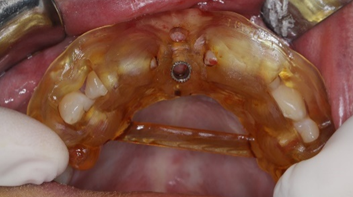

3. After disinfection, perform an intraoral trial fit of the guide to check if the pre-set window areas of the guide fit well with the teeth or other tissues. If not, adjust the obstructing areas and rinse for a trial fit. If it still does not fit well after adjustment, a new surgical guide needs to be made.

(Images provided by Dr. Zhu Xiao, Associate Chief Physician of the Department of Prosthodontics, Wuhan University)

4. Membrane-supported and bone-supported implant surgical guides need to be guided by occlusion. When positioning the guide, it is necessary to check if the occlusion is correct, if there is any displacement, and whether the guide is stable. Check for pressure points on the tissue surface, and ensure that the position of the retention pins is not interfered with by the buccal-labial muscles and is not too far back to complete the preparation of the retention pin channels.

5. During the trial fit, the stability of the guide should also be checked, especially for mixed-support and membrane-supported guides, to avoid any shaking during the implant surgery that could affect the accuracy of the implant placement. Additionally, check if the selected tools are appropriate and do not interfere with the surgical operation or compress the buccal-labial muscles.